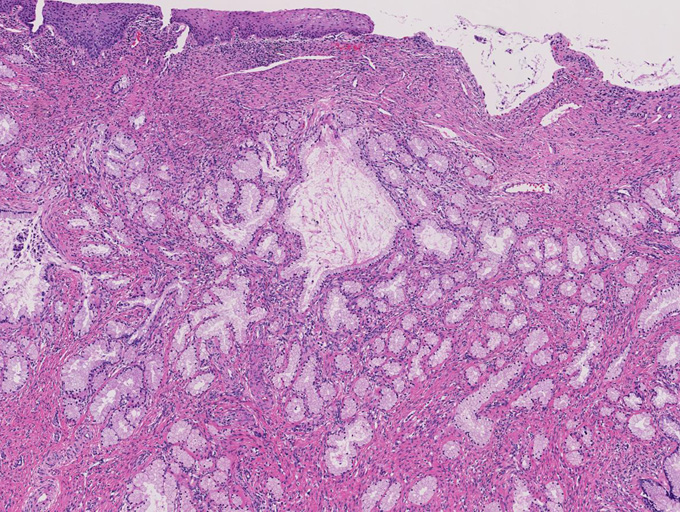

増生腺管上皮の細胞質は淡明ないし淡好酸性で, 核は小型で基底側に配列し、明らかな異型や重層化, 核分裂像を認めない。

腺管が破綻し, 間質への粘液逸脱と、それに対する間質反応も認めるが, この部分でも細胞異型は見られない。

しかしながら完全に異型がないとはいえず分葉構造を保持しているものの上皮の内腔への乳頭状増殖や重層化, 軽度から中等度の核腫大, クロマチン増加, 核分裂像をしめす腺が認められる---> with atypia

LEGHは大型導管に類似した拡張腺管の周囲に中型から小型の腺管が分葉状に増生するのが特徴。小型腺管を構成する高円柱上皮細胞質は正常頸管腺上皮の細胞質が淡明あるいは, やや青白い色調を呈するのに対し淡明ないし淡好酸性となる傾向にある。

核は小型円形で基底側に配列し典型例では異型, 核分裂像は認めない。

大型導管に類似した拡張腺管は胃の表層粘液細胞を, 周囲を取り囲む小型腺管は幽門腺細胞を摸倣しておりAB/PAS染色では一様に赤紫に染まり, HIK1083は後者でしばしば陽性となる。